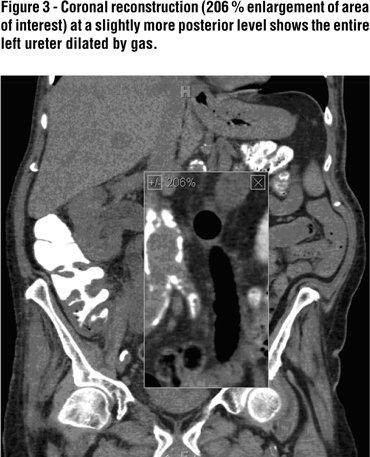

A three-phase contrast-enhanced CT (with intravenous contrast medium reduced to 60 mL, because of elevated creatinine) was performed with both coronal and sagittal reconstructions. An axial slice showed a hugely dilated left ureter with an air fluid level (Figure-1). A coronal reconstruction ( the area of interest enlarged to156%) demonstrates gas in the fistula to the thickwalled segment of the sigmoid colon as well as at the level of the UPJ (Figure-2). Diverticula are shown in the third portion of the sigmoid colon. An aneurysm of the infra-renal segment of the aorta was noted. Another coronal reconstruction (206% enlargement of area of interest) at a slightly more posterior level shows the entire left ureter dilated by gas (Figure-3). A sagittal reconstruction shows the dilated gas-filled left ureter (Figure-4).